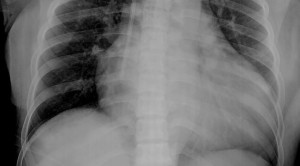

Cara membaca atau interpretasi rontgen toraks (chest x-rays) memerlukan pengertian anatomi dan fisiologi dari organ dada serta pengertian akan limitasi dari pemeriksaan...(Baca Selengkapnya)